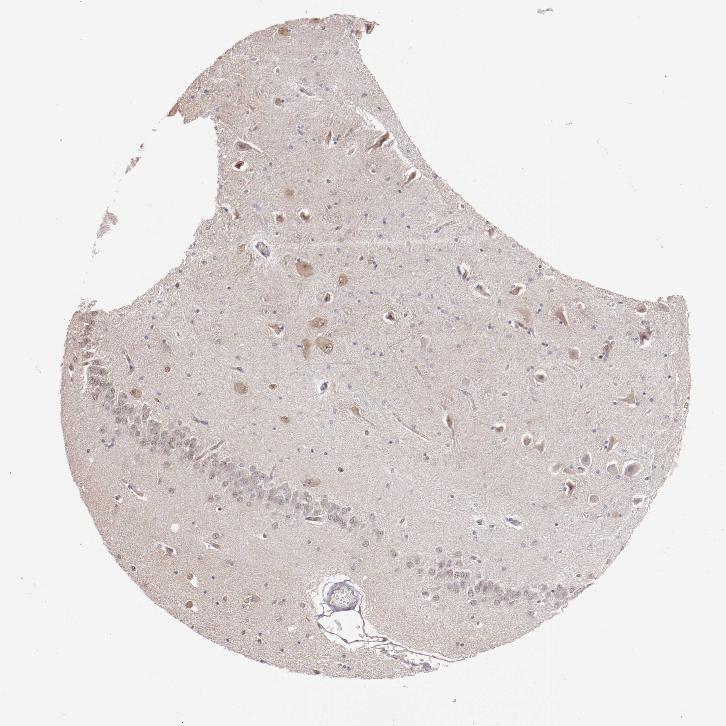

HIPPOCAMPUS - Antibody stainingi

Antibody staining in the annotated cell types in the current human tissue is reported as not detected, low, medium, or high, based on conventional immunohistochemistry profiling in selected tissues. This score is based on the combination of the staining intensity and fraction of stained cells.

Each image is clickable and will lead to virtual microscopy that enables deeper exploration of all samples and also displays staining intensity scores, fraction scores and subcellular localization as well as patient and tissue information for each sample.

Antibody HPA002191Antibody HPA069176

Glial cells Not detectedNot detected

Neuronal cells LowNot detected